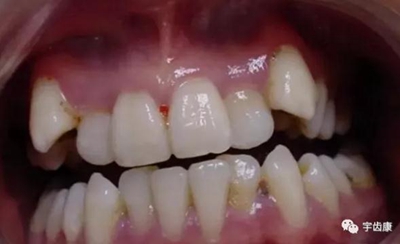

6. 保護(hù)牙周組織

保護(hù)牙周組織